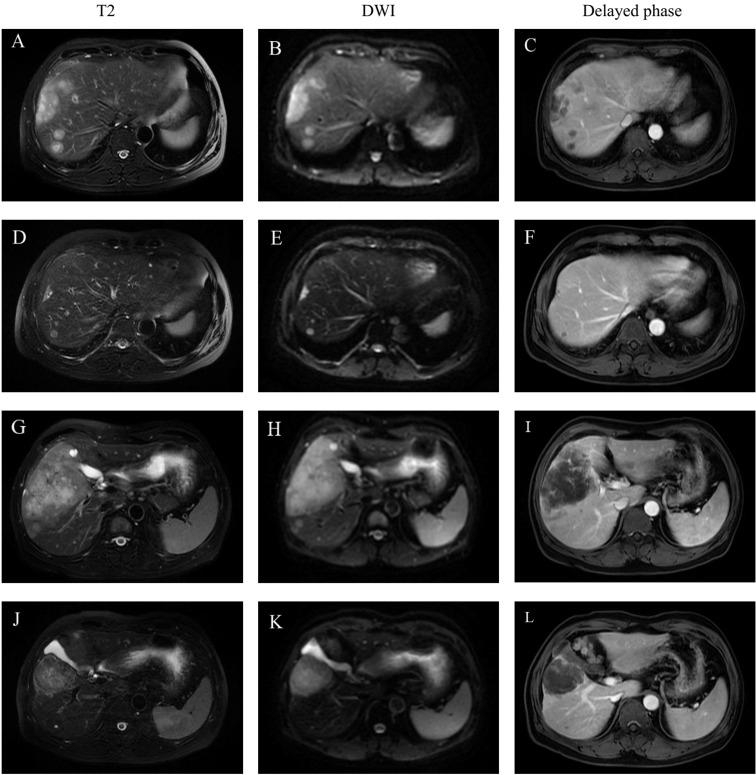

We reported a patient with unresectable ICC who received lenvatinib and pembrolizumab in combination with gemcitabine plus cisplatin (GP) chemotherapy and subsequently underwent radical liver resection. A 46-year-old male with a history of chronic hepatitis B and hypertension was diagnosed with ICC. Multiple liver tumors with ring-like enhancement were detected on abdominal contrast-enhanced CT and MRI. Enlarged lymph nodes were found in the hilar and retroperitoneal areas. The tumor was clinically staged as T2N1M0 (stage IIIB). Lenvatinib and pembrolizumab in combination with GP chemotherapy were adopted as first-line treatments for the patient. After six cycles of scheduled treatment, the diameter of the largest liver lesion and the number of liver lesions were markedly reduced. The level of the tumor marker CA19-9 decreased to a normal range. A partial response according to the mRECIST criteria was achieved without severe toxicities. Non-anatomical liver resection (segment 4b, 5,6 + segment 7 + segment 8), cholecystectomy and hilar lymph node dissection were performed one month after stopping combination therapy. Pathological examination confirmed a diagnosis of moderate-to-poorly differentiated ICC with lymph node metastasis. The patient has survived 15 months following resection of the tumors, with no evidence of local recurrence or distant metastasis.

我们报告了一例不可切除的 ICC 患者,该患者接受仑伐替尼和帕博利珠单抗联合吉西他滨加顺铂(GP)化疗,随后接受根治性肝切除术。一名 46 岁男性,有慢性乙型肝炎和高血压病史,被诊断为 ICC。腹部增强 CT 和 MRI 显示多个肝内肿瘤呈环形增强。肝门和腹膜后区域发现增大的淋巴结。肿瘤临床分期为 T2N1M0(IIIb 期)。仑伐替尼和帕博利珠单抗联合 GP 化疗被用作该患者的一线治疗方案。经过六周期的预定治疗后,最大肝病灶直径和肝病灶数量明显减少。肿瘤标志物 CA19-9 水平降至正常范围。根据 mRECIST 标准,达到部分缓解,无严重毒性。联合治疗停止一个月后,行非解剖性肝切除术(4b 段、5 段、6 段+7 段+8 段)、胆囊切除术和肝门淋巴结清扫术。病理检查证实存在中-低分化 ICC 伴淋巴结转移。患者在肿瘤切除后存活了 15 个月,无局部复发或远处转移的证据。